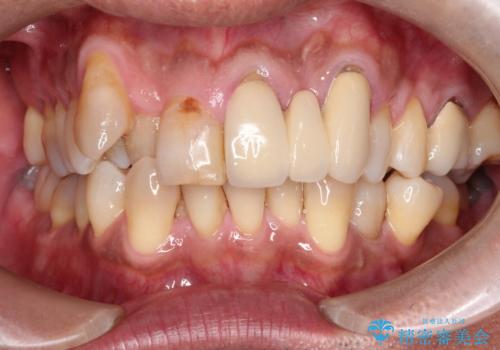

【インビザライン】前歯のガタガタを治したい

- 前歯のガタガタを主訴に来院されました。

上の歯の前突も気になってたため、奥歯の遠心移動も行いながらインビザラインにて治療を行いました。

前歯も下がり満足していただきました。

今回は奥歯の遠心移動とIPRを行って配列しています。